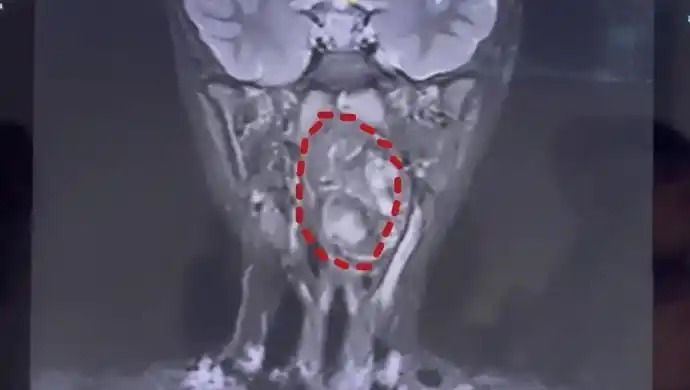

六岁男童的喉咙里长了一枚鸡蛋大小的肿瘤而这颗肿瘤竟然可能是孩子没有生长成型的双胞胎兄弟?!近日,复旦大学附属儿科医院成功为六岁男童小亮切除一枚鸡蛋大小的咽喉部畸胎瘤,历时三小时手术将肿瘤完整取出,术后5天小亮便基本痊愈,还出现了食欲大增的可喜变化。据小亮母亲刘女士介绍,半年前孩子开始出现异常,不仅每晚打鼾,而且越来越响,即便调整睡姿也无法缓解。还格外挑食,只爱吃面条、稀饭等软食,察觉不对劲后,她带孩子在当地医院检查,本以为只是咽喉腺体肿大,却被告知竟然是喉咙里长了鸡蛋大小的肿瘤,当地医院无法收治。慌乱中,母子俩前往复旦大学附属儿科医院就诊。经该院耳鼻咽喉头颈外科副主任陈超诊断,这枚肿瘤是由生殖细胞长成的畸胎瘤,“我们可以看出它有脂肪,有软骨,这是一对双胞胎,一个是正常发育成的人,另外一个可能残留在这个咽旁间隙里面,就发育成了这样的一个畸胎瘤。”

医生表示,畸胎瘤多为良性且常见于腹腔,长在儿童咽喉部且如此巨大的情况极其罕见。并且肿瘤还在长大,如不及时干预,孩子恐有生命危险。检查显示,小亮的口咽腔仅8厘米左右,而6.6×3.5×3厘米的肿瘤已占据大部分气道,仅留一条缝隙透气,若不及时手术,可能导致呼吸道梗阻窒息。更棘手的是,肿瘤紧贴颈内颈动脉,手术出血风险极高。医院随即联合麻醉科、重症医学科,制定个体化手术方案,通过口部进入并借助内镜辅助,将肿瘤分两块完整切除。医生提醒,儿童呼吸道梗阻并不罕见,家长需提高警惕。若孩子打呼噜时伴随睡眠不踏实、频繁翻身,或习惯趴着睡、仰头拉直脖子等特殊体位,可能是梗阻的明显信号,建议及时带孩子就医检查。在此提醒各位家长若孩子有难以解释的异常表现切勿简单归为体质或习惯问题及时排查才是关键